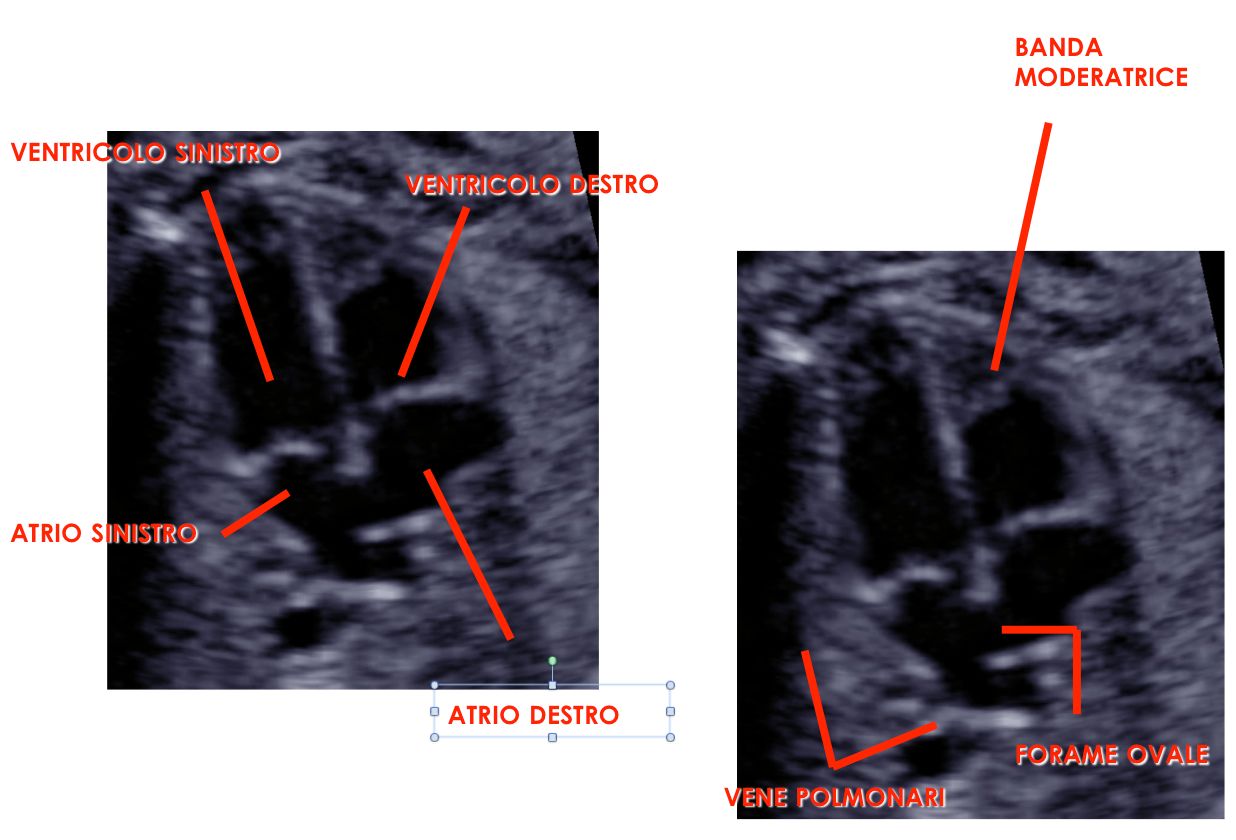

Sono esperta in ecografia 3D (tridimensionale) di cui sono stata docente a livello nazionale ed internazionale per oltre 20 aa, rivestendo incarichi nazionali nell'ambito della Società di Ecografia in Ostetricia e Ginecologia (SIEOG).

ecografia 3D Da 260 €

ecocardiografia fetale Da 260 €